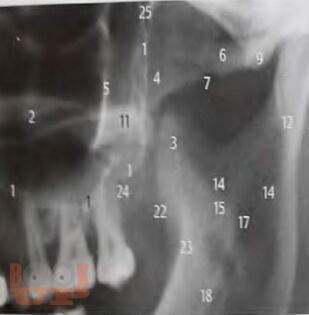

В учебно-методическом пособии представлен доступный алгоритм лучевой диагностики при синдроме болевой дисфункции височно-нижнечелюстного сустава. Алгоритм дает возможность повысить точность диагностики, а следовательно, и эффективность лечения пациентов, индивидуализировать методы терапии каждого больного.

Пособие предназначено для врачей разных специальностей: стоматологов, неврологов и рентгенологов, а также интернов и ординаторов.